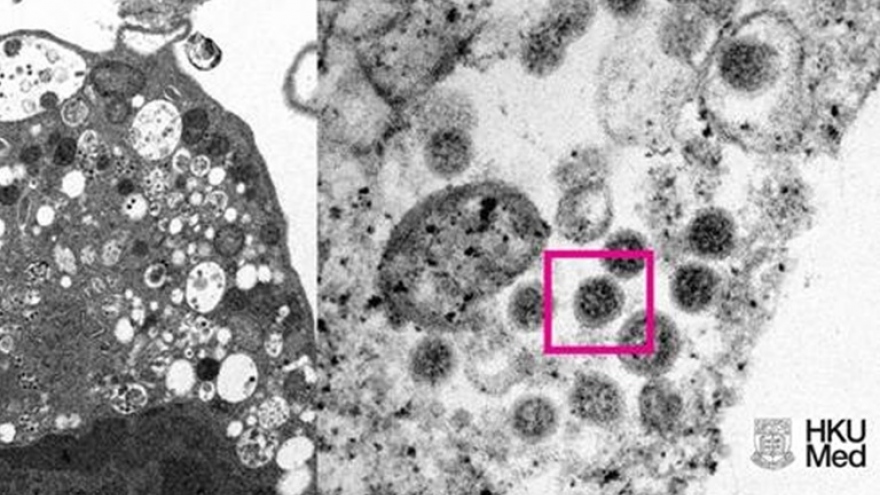

VOV.VN - Biến thể Omicron của virus SARS-CoV-2 đang tiếp tục lan rộng tại châu Âu và thế giới. Theo thống kê, cứ 2 đến 3 ngày số ca nhiễm Omicron lại tăng gấp đôi tại Anh và Đan Mạch, trong khi Mỹ cũng ghi nhận 25 bang có số ca mắc biến thể này.